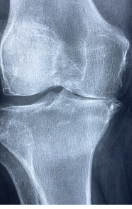

연골은 뼈와 뼈 사이에서 매끄러운 움직임을 위해 존재하는 연결 조직으로, 인간의 근골격계를 구성하는 중요한 요소 중 하나입니다. 연골은 충격을 흡수하고 뼈의 마찰을 감소시켜 관절 부상을 방지하는 역할을 합니다. 또한 연골은 영양분을 받기 위해 관절에서 분비되는 관절액을 통해 영양분을 공급받아 생존합니다. 그러나 연령이 들면서 연골 조직은 변성되어 내구성이 감소하고 탄성이 낮아지며, 이로 인해 관절염 등의 질병이 발생할 수 있습니다.

무릎은 몸을 지탱하고 이동하는데 중요한 역할을 합니다. 이러한 기능을 수행하는 것은 힘든 일이며, 이를 수행하는 무릎 관절은 매우 복잡합니다. 이에 따라 무릎은 매우 취약한 부위 중 하나입니다. 무릎 연골 손상은 무릎 관절에서 연골 손상이 발생하는 상황을 말합니다. 이는 수많은 원인으로 인해 발생할 수 있습니다.